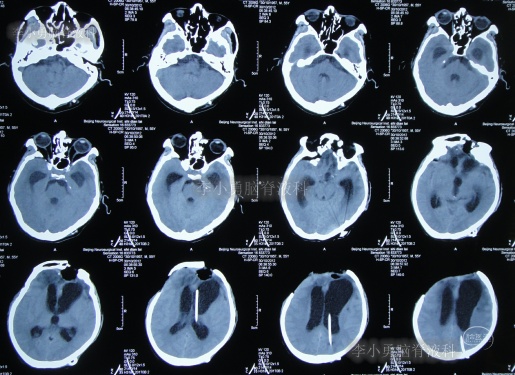

2012年11月1日(开颅术后126天即脑室腹腔分流术16天),转住入李小勇脑脊液科入院时:神志模糊,表情淡漠,肢体不能遵嘱活动,时常有癫痫发作;右额颞顶颅骨缺损,缺损相应区域局部凹陷,自右侧鼻唇沟至头顶有一疤痕,右侧额面部颅骨凹陷(图-6)。头颅CT:脑室腹腔分流术后改变,脑室扩张(图-7)。

图-7:入院时头颅CT

2012年11月5日(入院后5天),进行了原脑室腹腔分流管去除术(右)+侧脑室外引流术(右)。

术后次日查头颅CT示脑室外引流术后(图-8);血培养(厌氧菌):溶血葡萄球菌感染。

图-8:2012年11月6日头颅CT

2012年11月23日(入院治疗23天),引流出血红色脑脊液(图-9);查头颅CT示脑室有缩小(图-10)。

图-10:2012年11月23日头颅CT

2013年1月14日(入院治疗75天),进行了左侧脑室腹腔分流术(图-11);

图-11:2013年1月14日术后头颅CT

2013年1月17日(入院治疗78天),晚上19点左右,患者突发意识障碍、右侧肢体偏瘫,头部外引流管流出粉红色液体,急查头颅CT示左额颞顶区硬膜下血肿,蛛网膜下腔出血(图-12)。于当晚急诊全麻下进行“左额颞顶硬膜下血肿清除术”。

图-12:2013年1月17日头颅CT

术后患者仍处于昏迷状态;次日2013年1月18日晨起,颅骨缺损处张力较高,复查头颅CT示术区无明显再出血,左顶叶硬膜外血肿,术区脑组织肿胀(图-13),当天进行了左额颞顶硬膜下血肿清除术后,左顶叶硬膜外血肿(图-14)。

图-13:2013年1月18日头颅CT

图-14:2013年1月18日术后头颅CT

2013年1月22日(入院治疗83天),患者术区引流管引流液极少,复查头颅CT脑室较前稍有扩张,右侧骨窗张力仍较高(图-15),进行了侧脑室外引流术(右)+左额颞顶硬膜下引流管去除术+左顶硬膜外引流管去除术。

图-15:2013年1月22日头颅CT

2013年1月25日(入院治疗86天),查头颅CT示脑室有缩小(图-16)。

图-16:2013年1月25日头颅CT

2013年1月31日(入院治疗92天),查头颅CT示脑室进一步缩小,骨窗塌陷(图-18)。

图-18:2013年1月31日头颅CT